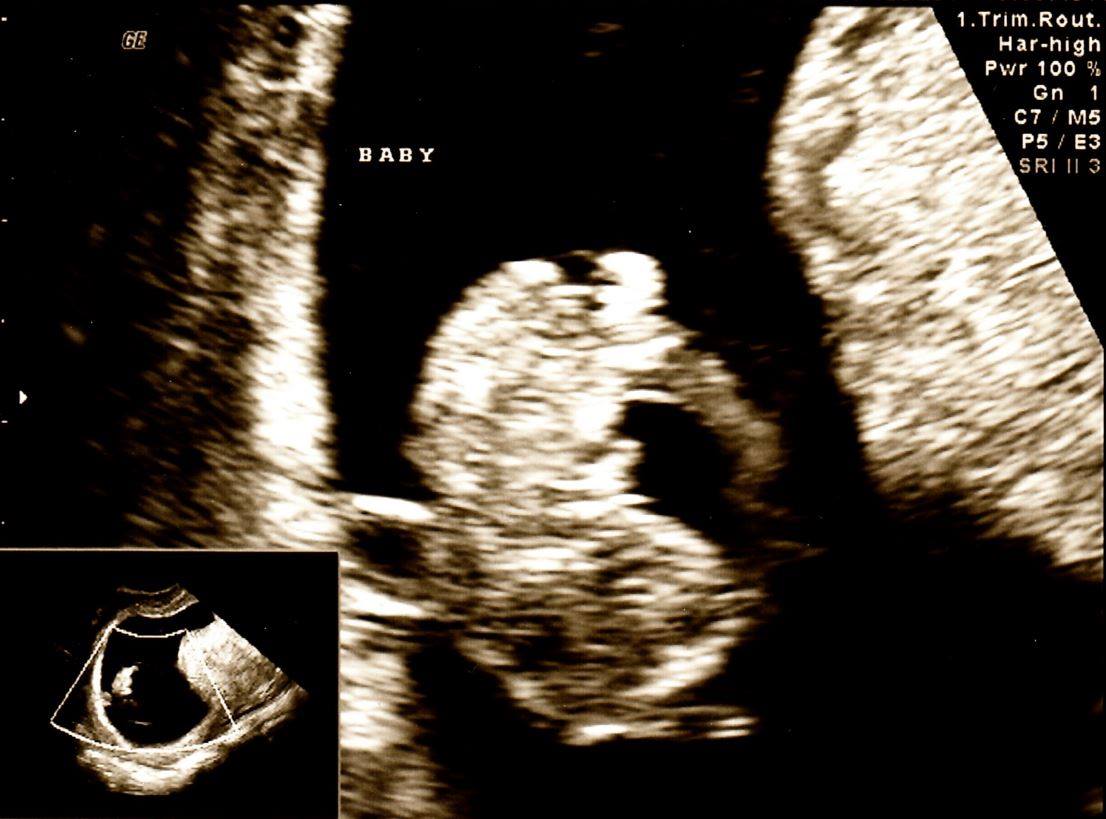

6. Fetal pain addresses our humanity, & humanity demands human rights.

Some vilify the death penalty for a few criminals condemned publicly in a court of law

but defend destruction of millions of unborn children as a private issue 2 b decided between a woman & her abortionist

Some vilify the death penalty for a few criminals condemned publicly in a court of law

but defend destruction of millions of unborn children as a private issue 2 b decided between a woman & her abortionist

7. The tried & condemned will, before a crowd of somber witnesses, receive anesth b4 lethal inject'n, time of death recorded, body receiving a resp'ful burial.

Unborn child gets no anesthesia before being quietly dismembered in her mother's womb, her tiny parts heaped on a tray

Unborn child gets no anesthesia before being quietly dismembered in her mother's womb, her tiny parts heaped on a tray